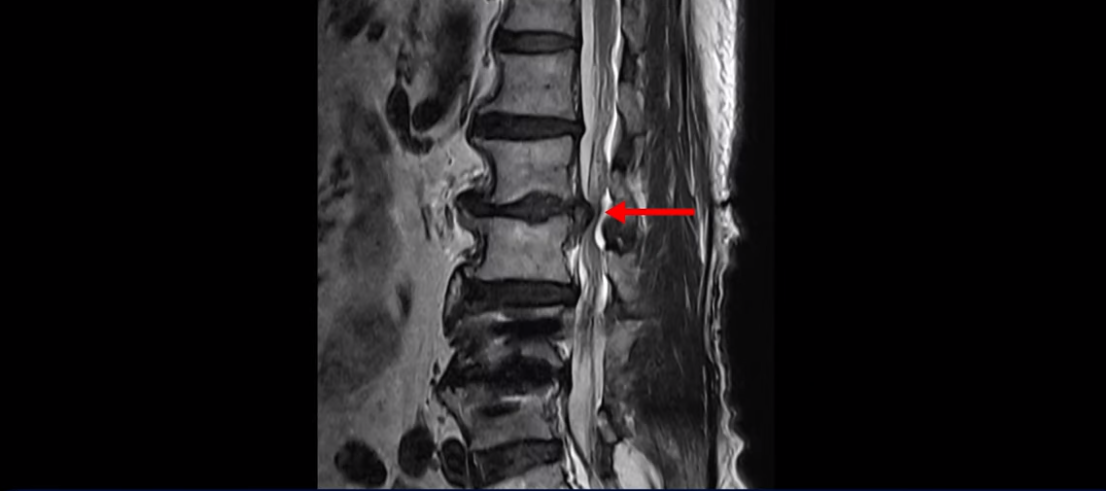

이분 허리 MRI를 보면서 간단히 설명드린 후 유합술 이후 인접마디에 문제가 생긴 환자분들이 왜 추가적인 수술을 서두르기보다는 허리기능을 살려주는 근육신경재활치료를 받는 게 좋은지, 또 치료는 어떻게 하는 게 좋은지 자세히 설명드리겠습니다. 이분 MRI를 보면 4번 5번에 나사가 박혀있습니다.

이렇게 나사가 박혀있으면 그 위나 아래에 문제가 많이 생기고 그걸 인접분절질환이라고 부릅니다. 이분도 유합술을 받은 그 윗마디인 2번 3번에서 디스크가 터져 밀려나와서 수술을 받았는데

이게 수술 후 사진인데도 여전히 척추관은 좁습니다.

나사 박은 마디 위쪽에 수술을 받았지만 수술 후에도 전혀 통증이 좋아지지 않고 다리에 힘도 빠져서 워커를 잡고 겨우 걷는 상태였습니다. 이렇게 유합술 이후 그 위나 아래에 문제가 생기는 인접분절질환은 모든 척추질환 중 가장 치료가 어려운 질환 중 하나로 꼽힙니다.

척추에 유합술을 해서 허리의 기능, 특히 근육의 기능이 많이 떨어진 환자들은 허리의 기능이 많이 떨어질수록 추가적인 수술을 해도 또다시 통증을 겪을 가능성이 높아집니다. 이런 통증을 척추수술 후 실패증후군, 또는 척추수술 후 통증증후군이라고 부릅니다. 허리의 기능이 많이 떨어질수록 수술로 신경 눌린 것을 잘 풀어줘도 여전히 아플 수가 있습니다. 이분도 역시 수술한 부분 위에서 디스크가 터졌다고 해서 수술을 받으셨는데 수술 후에도 통증은 똑같이 남아있습니다. 수술한 의사는 수술이 잘 됐다고 왜 아픈지 모르겠다고 하니까 환자만 답답한 겁니다.